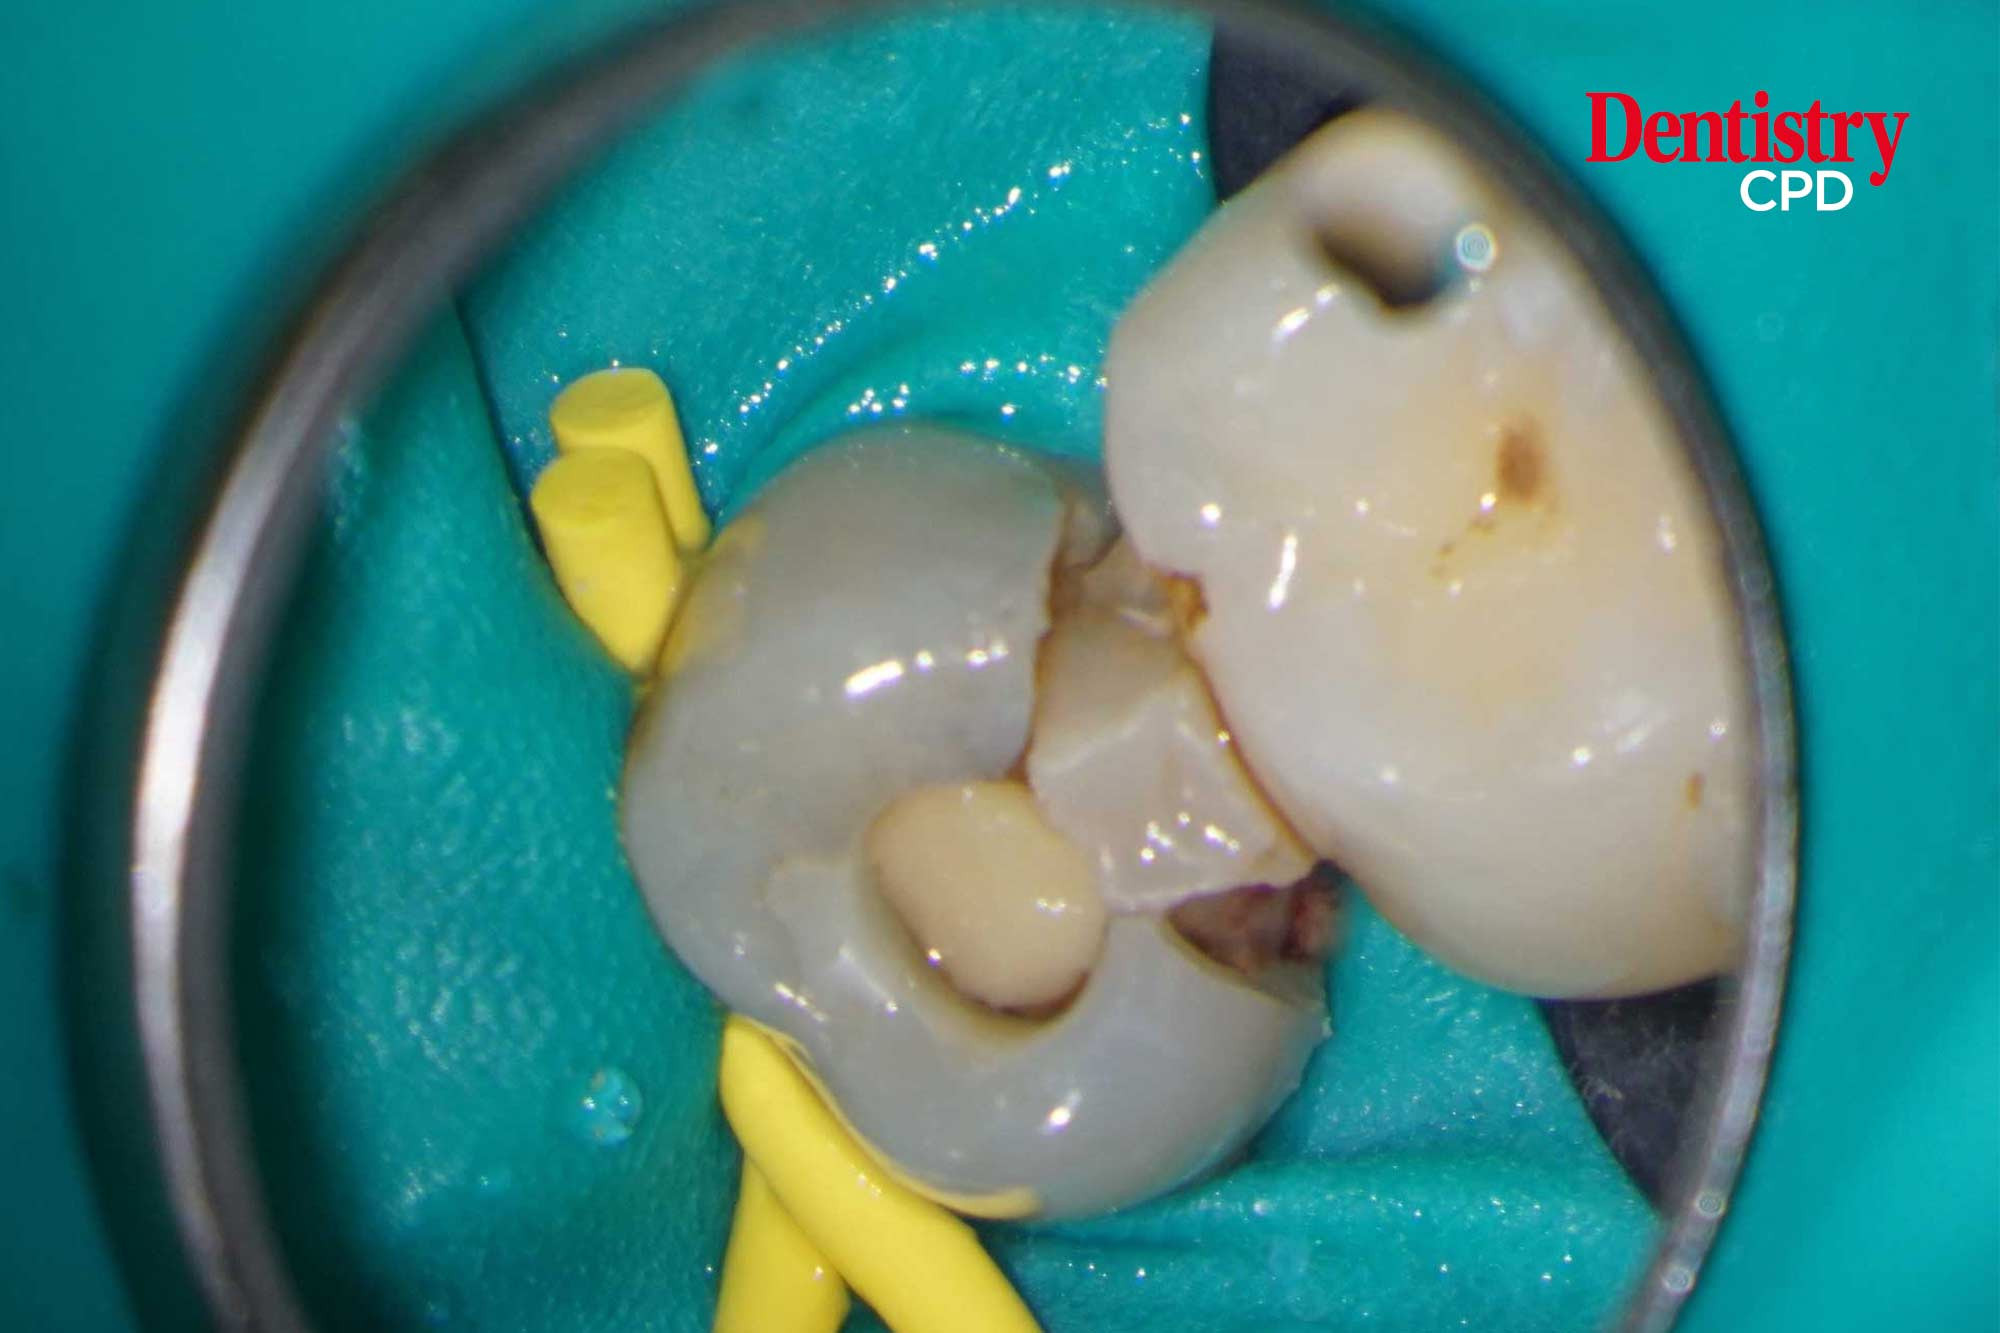

John Rhodes looks at the non-surgical root canal re-treatment of a maxillary premolar with hidden obstacles and unusual morphology.

To show how obstacles and root canal morphology can be negotiated during non-surgical root canal re-treatment.